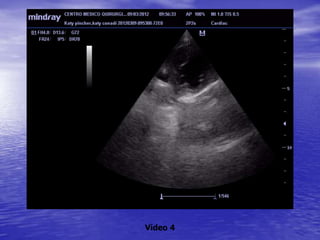

ECOCARDIOGRAFIA

Vídeo 4